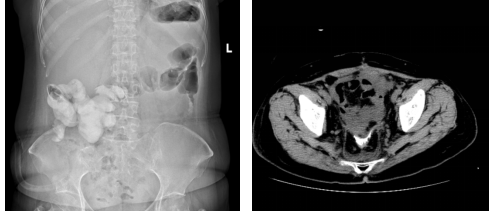

术后腹部平片可见小肠支架完全降解(左),肠道造影发现吻合口愈合良好(右)

于爱军团队凭借谨慎的术前评估、个体化的手术方案和高超的手术技术,于2025年7月成功为患者邓女士施行了肿瘤细胞减灭术,并应用支架法肠转流术替代了传统造口。术后第二周复查CT及腹部平片可见,完整支架影在妇科肿瘤外科、营养科及护理团队的通力合作下,患者G女士术后恢复迅速,顺利进食,转流管引流通畅。术后复查显示支架位置良好,肝肾功能等指标稳定,并于术后第三周如期开始了首次静脉化疗。术后第四周,影像学证实支架已完全降解,转流管成功拔除,患者进食半流质后一切正常,吻合口愈合良好。